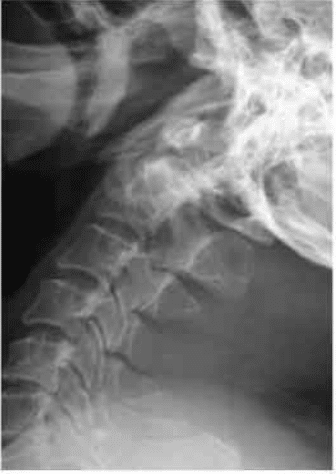

On follow up, he gradually recovered his function and is now able to use chopsticks and has gone back to drive a lorry.